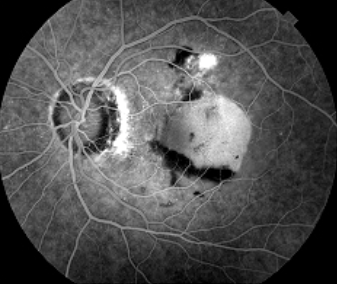

• A leak occurs when there is loss of fluorescein into the extracellular space. A full leak begins early in the scan and increases in size and intensity with time. Pooling and staining are types of leaks with defining characteristics explained below.

• Defined as the accumulation of leaked fluorescein within a defined anatomical space. Once this defined space is filled, the margins in pooling remain constant and distinct throughout the study (unlike full leaking which continues to grow as the scan progresses).

• Neovascularization and fibrosis.

• Intraocular inflammation.

• Tumours of the disc, retina and choroid if the integrity of the retina has been interrupted.